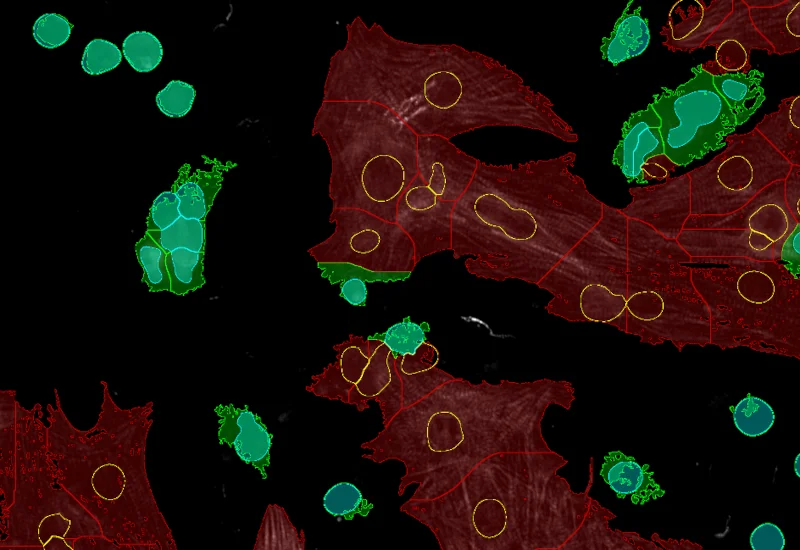

Original Image

Nuclei detection

Dot detection

Cardiomyocytes (red), fibroblasts (green)